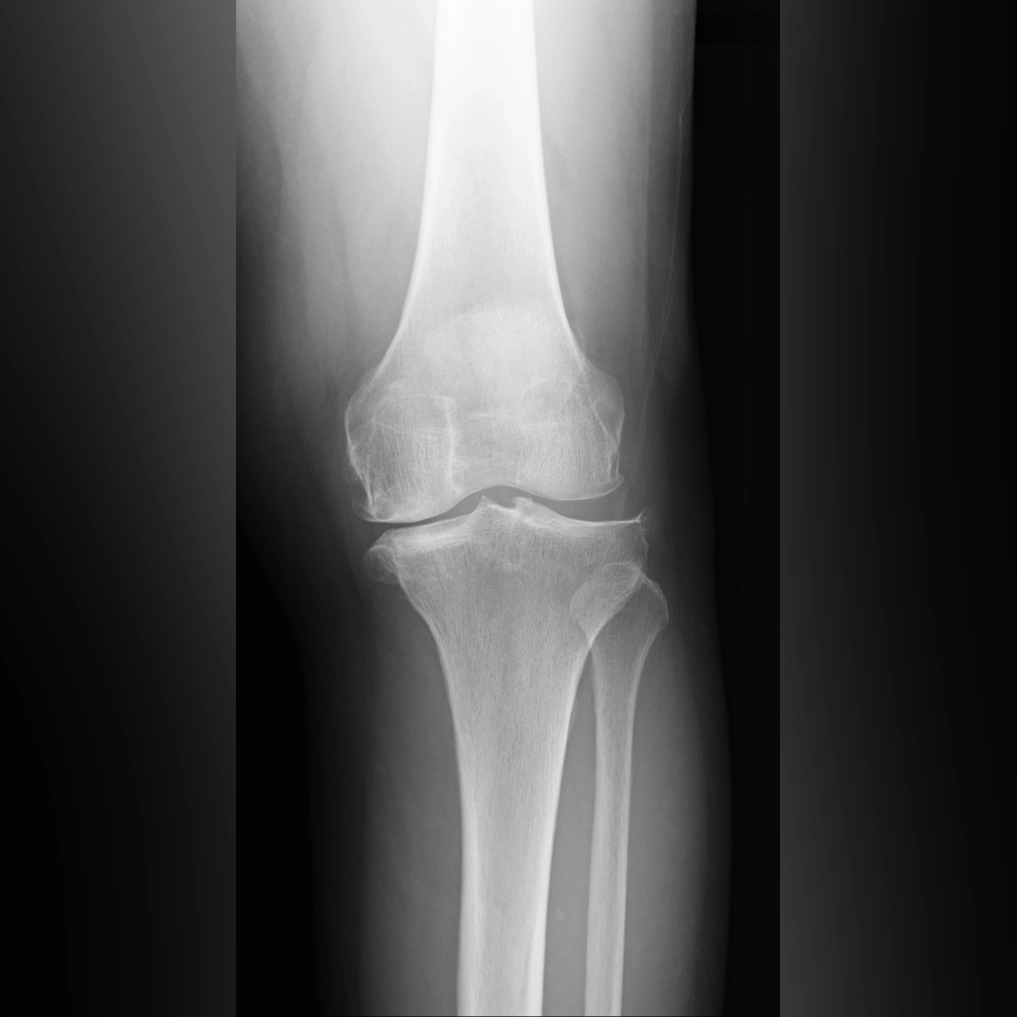

ひざ関節は、大腿骨と脛骨の間の隙間の部分です。レントゲンではこの部分が隙間として写りますが、実際には関節軟骨と半月板が存在します。立位で体重をかけて撮影した場合、この隙間の広さがおおよそ関節軟骨の厚みを示すと考えてよいでしょう。この大腿骨と脛骨の隙間のうち、腓骨に近い側を外側関節、腓骨から遠い側を内側関節と呼びます。また、脛骨の中央には2つの小さな山のような部分が見えますが、ここには前十字じん帯と後十字じん帯がついています。

※レントゲン画像左が内側、右が外側

O脚変形がみられる場合、初期のレントゲンでは外側関節に比べて内側関節の隙間がやや狭くなっています。これは内側の軟骨が少し減ってきた状態を示しています。